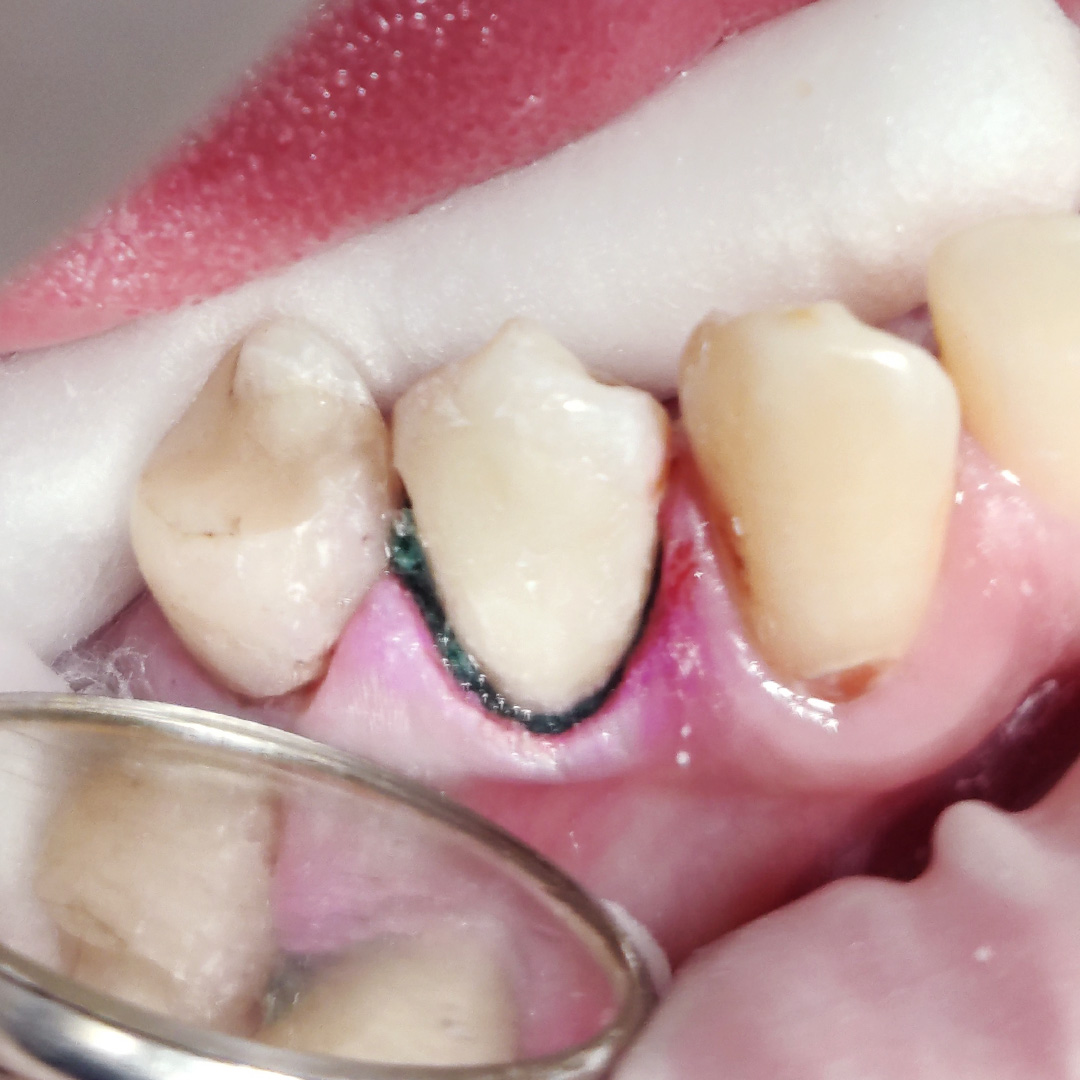

Пациент обратился с жалобой на эстетический недостаток в области нижнего зуба справа. После обработки кариозной полости врач выявил глубокий кариес. Дно и стенки полости плотные, гладкие, блестящие, при зондировании крепетируют. Реакция на холод слабоболезненна, на перкуссию — безболезненна. Диагноз — хронический глубокий кариес.

Ход лечения:

- введение анестезии Sol. Articaini vs. Adrenalini 1:200000 1.8 ml;

- наложение системы OptaGate;

- установка ретракционной нити UltraPack 00;

- механическая обработка кариозной полости;

- медикаментозная обработка полости раствором хлоргексидина 2%;

- пломбирование Vitremer (A3);

- микроконтурирование и макроконтурирование пломбы.